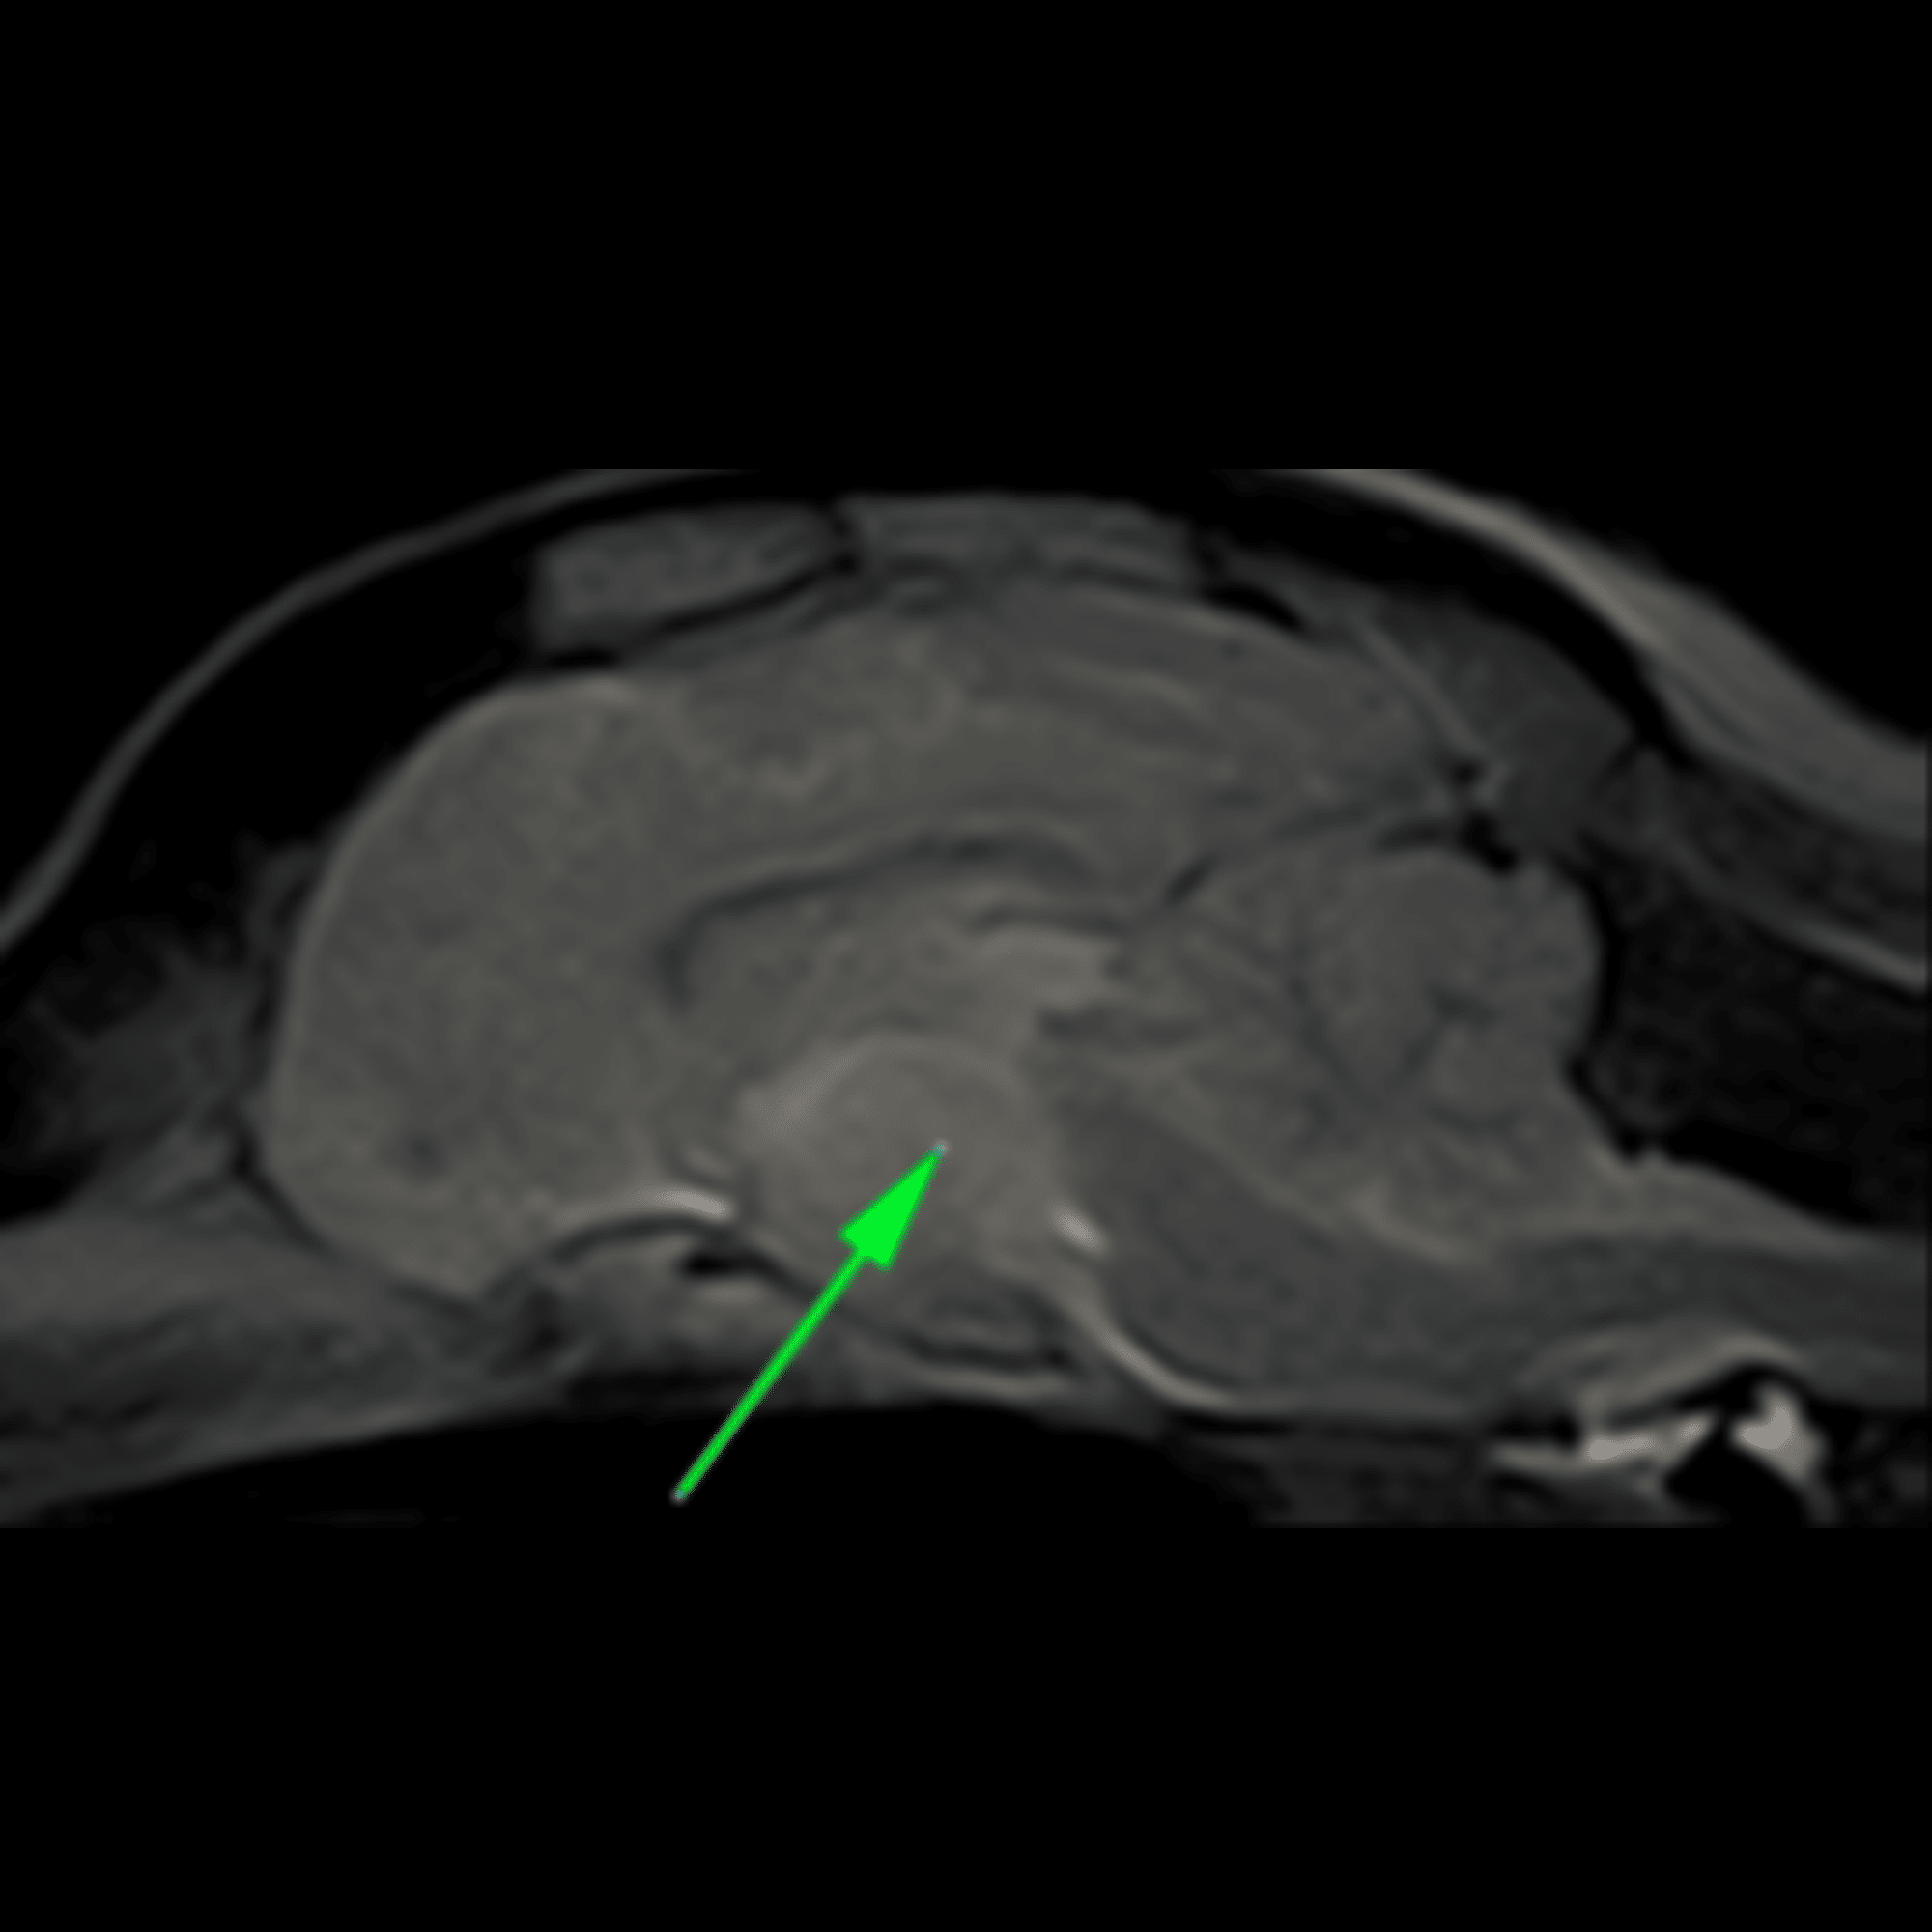

Le scanner et l’IRM

Enfin le scanner et l’IRM (imagerie par résonance magnétique) sont des examens d’imagerie en coupe effectués sous anesthésie générale. Effectués au sein même CHV Frégis, ces examens sont déterminants pour le diagnostic de maladies d’origine nerveuse responsables de cécité ou encore celui de maladies de l’orbite (cavité osseuse hébergeant l’œil dans sa partie antérieure).

La flèche indique une tumeur bénigne de l’hypophyse dans le cerveau, responsable d’une cécité chez un chien (image IRM).